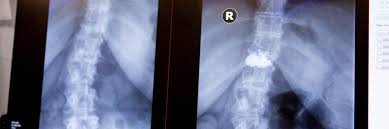

Schmerzen im bein nach spinalkanalstenose op. Starke Schmerzen im Bereich der Beine und auch Rücken sind ebenfalls häufig. Die klassische spinale Stenose äussert sich in Schmerzen in einem oder beiden Beinen die nach einer bestimmten Gehstrecke oder Zeit im Stehen auftreten. In einigen Fällen ist eine OP unvermeidlich.

Die wichtigsten Tipps im Umgang mit Spinalkanalstenose. Durch Abnutzungserscheinungen der kleinen Wirbelgelenke der Bandscheiben im Alter durch Bewegungsmangel oder Veranlagung daraus folgt kein langer Spaziergang das Kreuz tut weh Schmerzen ziehen bis in die Beine. Viele Patienten mit einer Spinalkanalstenose klagen neben Schmerzen in den Beinen beim Gehen über eine Schwäche und ein Schweregefühl der Beine.

Die wichtigsten Symptome einer Spinalkanalstenose sind belastungsabhängige Rückenschmerzen und Beinschmerzen hauptsächlich beim Gehen Stehen und. Bei einer Spinalkanalstenose kommt es zu Schmerzen im Bein beim Gehen Tipps zur Vorbeugung und Selbsthilfe alles zu Symptomen. Meine Schmerzen die in die Beine ausstrahlten waren sofort nach der OP weg.

Wenn Schmerzen im Bein sehr gefährlich sind. Die Belastungsfähigkeit ist herabgesetzt. Kreuzschmerzen und ein Ausstrahlen dieser Schmerzen in die Beine sind Symptome einer Spinalkanalstenose.